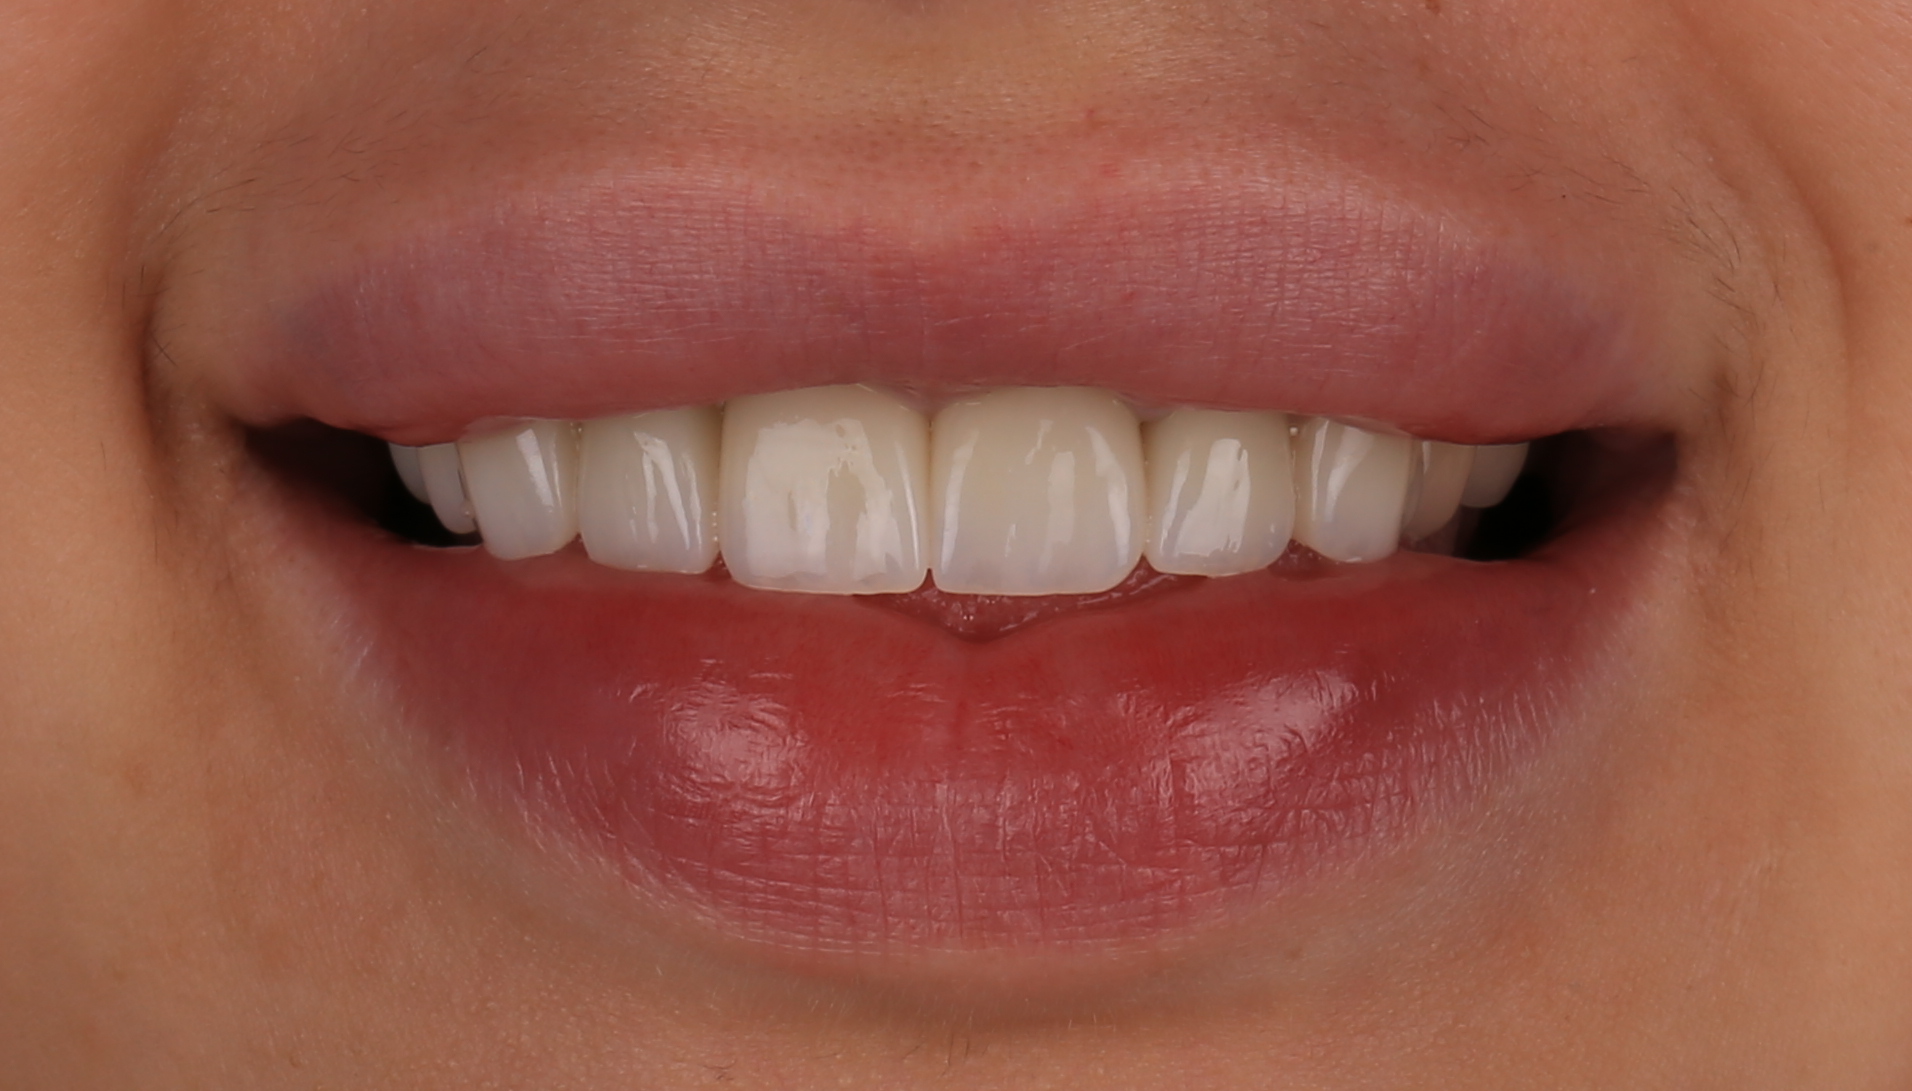

Вініри E-max.

Вініри — естетичне рішення для ідеальної посмішки. Мінімальне втручання, максимальний результат.